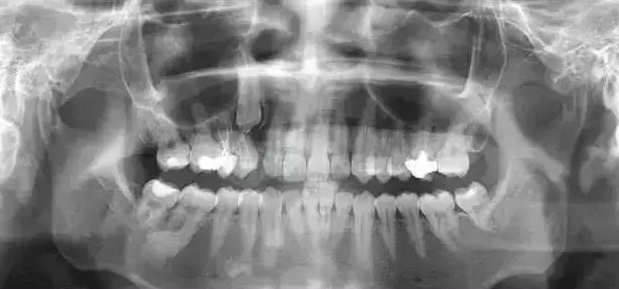

02、全景片(曲面断层片)

拍摄全口牙齿,二维成像,可将全口牙齿的体层影像,双侧上下颌骨,上颌窦,颞颌关节等同时显示在一张胶片上。